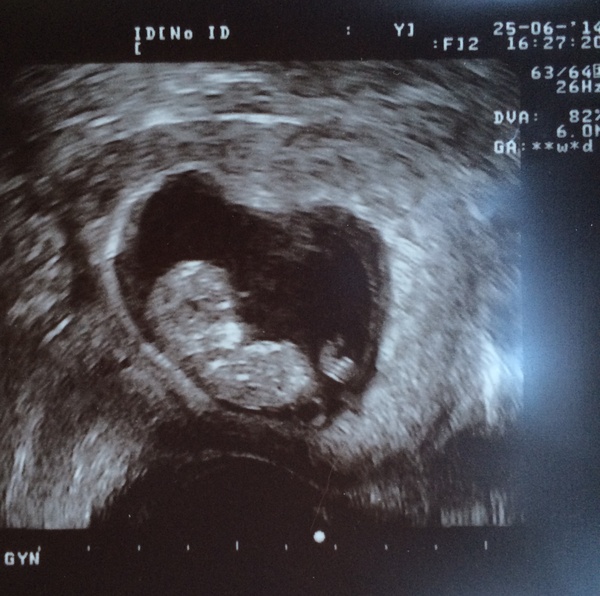

helloelo what a cute scan photo, and lovely happy story for the anxious lurkers out there.

11+1